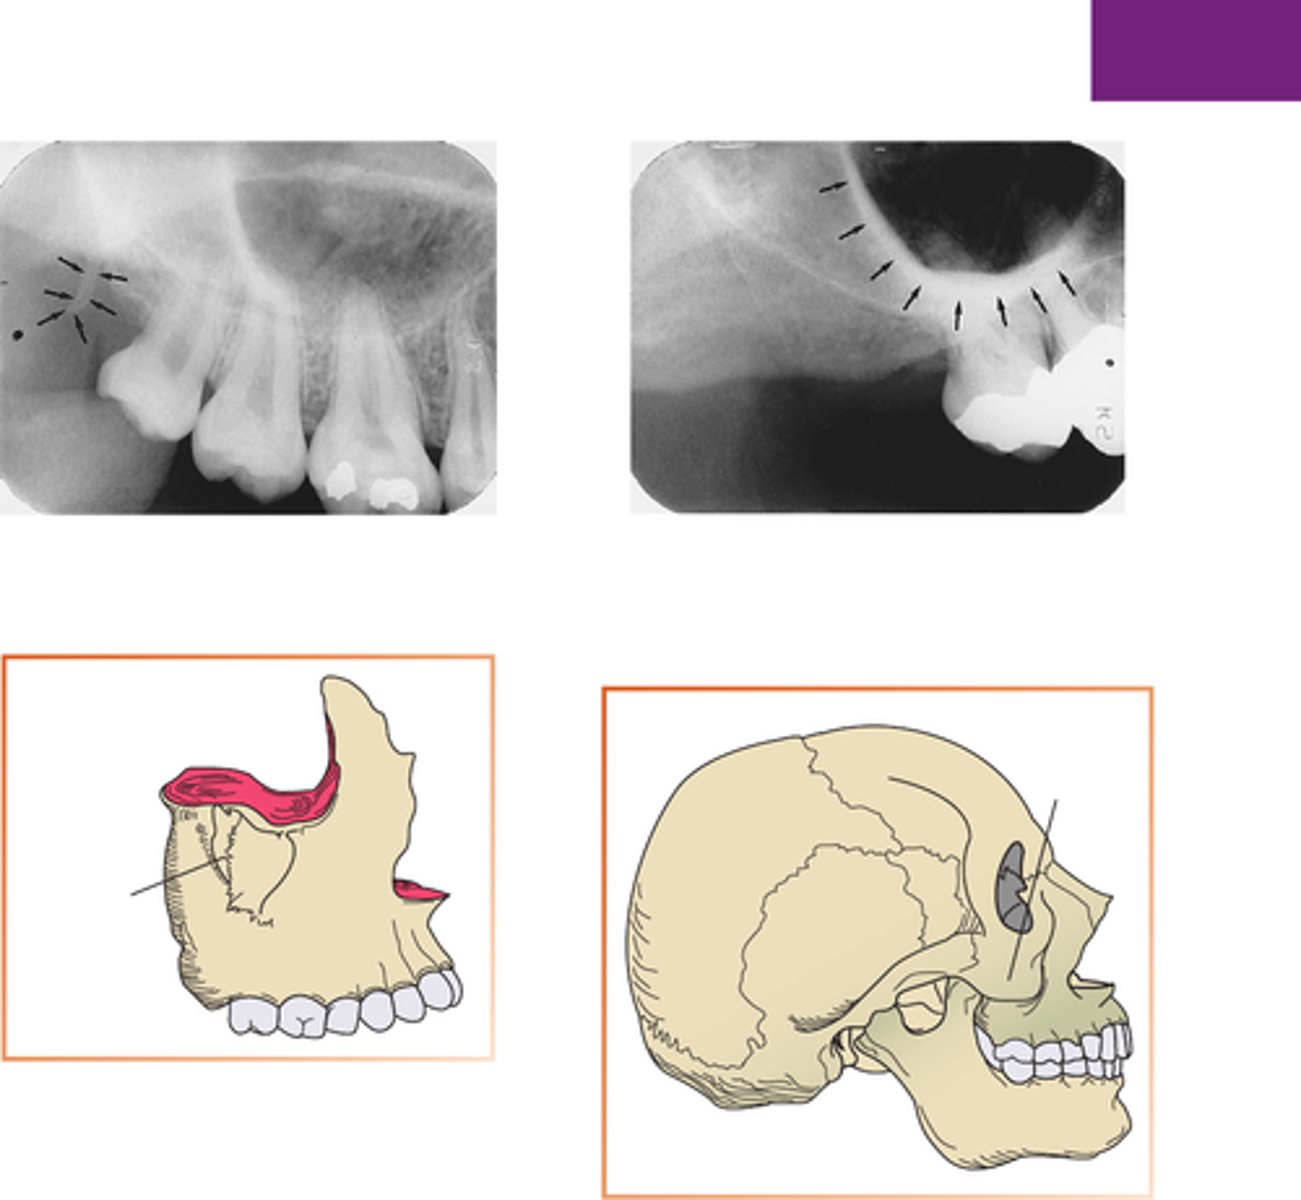

Zygomatic process

What is the radiopaque structure seen in the upper right picture?

Hamulus

What is the radiopaque structure seen here?